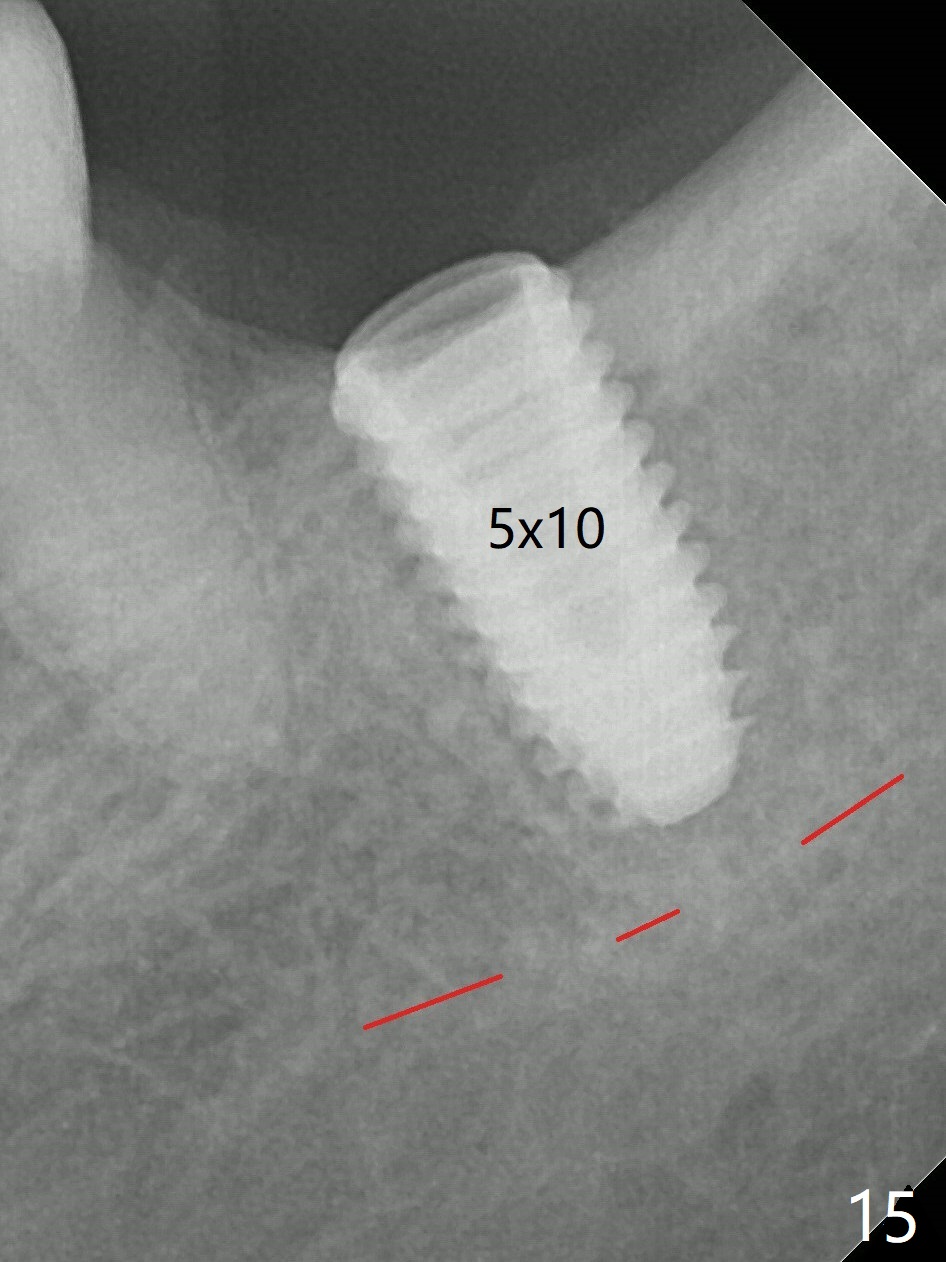

There is no apparent bone loss 4 months postop (Fig.10). There is chewing pain in spite of occlusal adjustment 7 months post cementation (Fig.11-13: increased radiolucency around the implant). The crown/abutment is removed and a healing abutment is placed (6x3 mm); the implant is stable. The patient return for re-evaluation in 3 months (15 months postop); radiolucency appears to reduce (Fig.14). But there is pain when the healing abutment is being removed. After local anesthesia, the implant is removed with a wrench. Following debridement of the osteototomy (intact, although tender), a 5x10 mm dummy implant with SLA surface is placed (Fig.15). After 5.5 mm tap, a 5.5x8.5 mm implant is placed with >50 Ncm (Fig.16). A 6.8x5 mm healing abutment is placed, followed by periodontal dressing. Re-analysis of preop CBCT shows that the bone density at the site is low: 70 units average. Progressive loading is necessary for this case 4-6 months postop. The soft and hard tissues around the implant seem to heal 4 months postop (Fig.17).